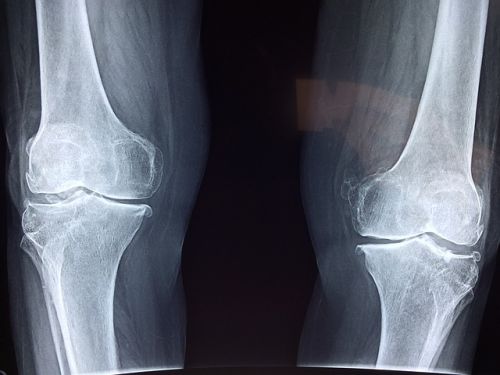

한국은 고령화가 빠르게 진행되고 있고, 이에 따라 무릎 퇴행성 관절염을 앓는 인구도 꾸준히 증가하고 있습니다. 이런 상황에서 고가의 인공관절 수술은 저소득층에게 큰 부담이 되죠. 바로 이 지점을 해소하기 위해 마련된 것이 바로 본 사업입니다.

다음으로 질환 조건입니다. 일반적인 무릎 통증이 아닌, 건강보험급여 ‘인공관절치환술(슬관절)’ 인정기준에 해당되는 진단을 받아야 합니다. 다시 말해, 단순한 통증이나 타박상으로는 안 되고, 정형외과에서 ‘퇴행성 관절염’, ‘심한 무릎연골 마모’ 등으로 인해 인공관절 수술이 필요하다는 소견이 나와야 하는 거죠. 이 소견은 반드시 의사의 진단서 또는 소견서로 증명돼야 하며, 수술 예정 병원에서 발급받을 수 있습니다.